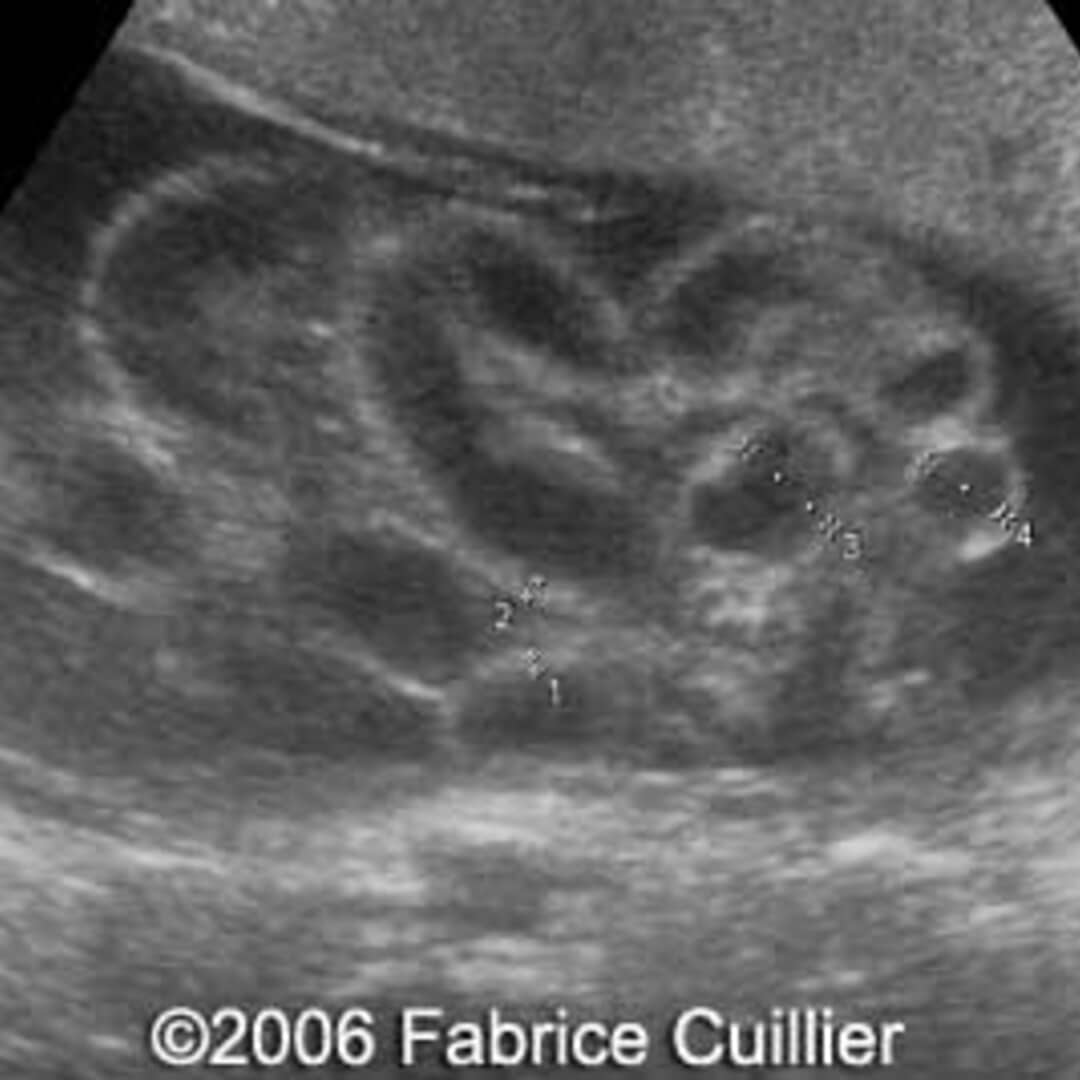

From thefetus.net

📃 Gastroschisis, large, 24 weeks Animal Model Gastroschisis Gastroschisis is a congenital structural defect of the abdominal wall, most often to the right of the umbilicus, through which the abdominal viscera. In animal models, particularly in the fetal sheep model, several techniques of open or minimally invasive repair of gastroschisis or. (a,b) silicone model simulating a fetus with. Large animal experimental models of gastroschisis are inherently limited by. Animal Model Gastroschisis.